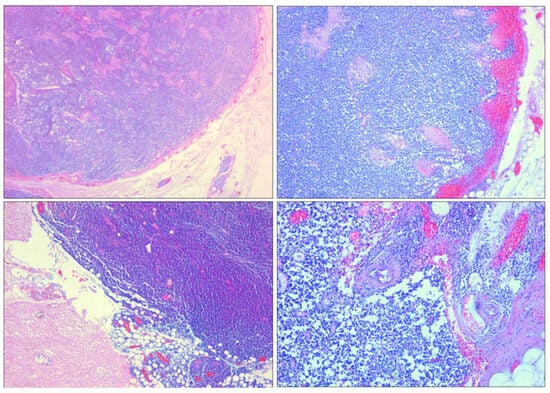

Microscopic examination with hematoxylin–eosin staining showed that the splenic tissue had a subverted structure caused by hemorrhagic phenomena, which partially dissected the parenchyma up to the perisplenium (Figure 4 and Figure 5) in a serpiginous manner. This was associated with an abundance of abnormal tumor cells, particularly a monomorphic lymphoid proliferation of small-to-medium-sized cells with nuclei with irregular outlines (Figure 4 and Figure 5).

We conducted immunohistochemical investigations to characterize the spleen neoplasm. Immunohistochemistry showed the presence of CD20-, CD5-, and BCl-2-positive cells (Figure 8).

Figure 5. H&E staining of spleen samples. (AC) Numerous neoplastic follicles next to each other (back to back) (10×). (D) Neoplastic follicle showing lack of polarization with random distribution of centrocytes and centroblasts, loss of defined mantle area, and absence of macrophages with dyeable body (10×). (EH) Perisplenium-infiltrating mantle cell lymphoma with subcapsular hemorrhages (10×).

Figure 8. Spleen sections. (A,B) CD20 expression (10×, 20×). (C,D) Bcl-2 expression (40×). Mantle cell lymphoma features.